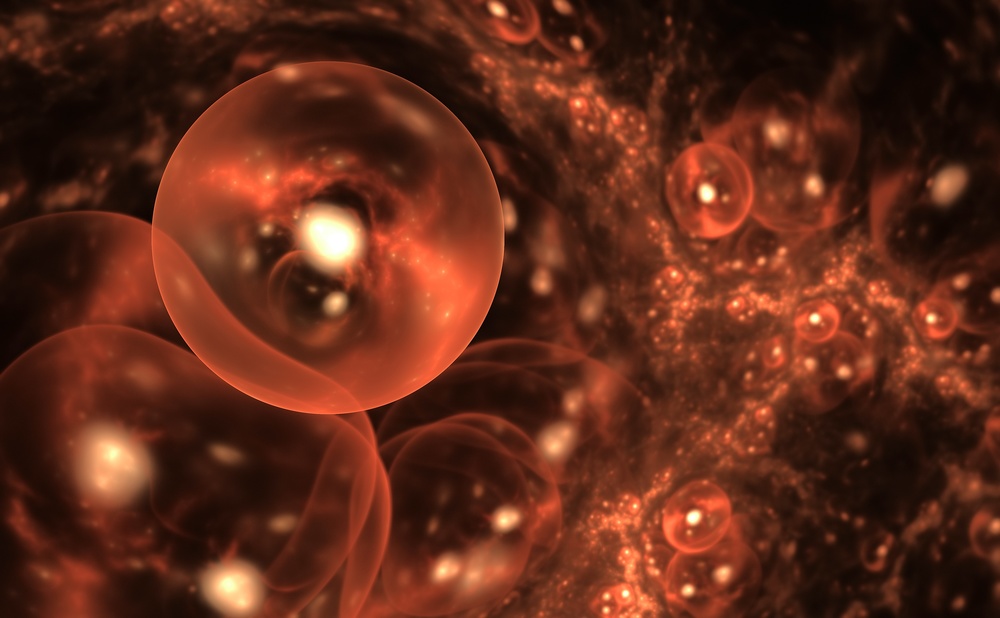

Липидная мембрана клетки — основа клеточной оболочки любого живого организма — это удивительный умный «забор», через который клетка общается с организмом, питается, дышит, защищается от вторжения интервентов и чужаков, впускает нужные вещества и закрывается от нежелательных. Это целый комплекс security-мер с избирательным воздействием. Основной инструмент этой биохимической «коммуникации» — поры, опциональные отверстия в мембране. Своеобразный пропускной шлюз, который ученые активно изучают и описывают, чтобы в дальнейшем управлять им в собственных — благих, разумеется, целях.

Липидные мембраны — это оболочки, которые отделяют клетки и их органеллы от внешней среды. Эти структуры выполняют ряд важных функций жизнедеятельности, в частности становятся барьером, который контролирует обмен веществ клетки. Возможные нарушения этого барьерного механизма давно и активно изучаются в свете разработки лекарств и терапевтических стратегий, таких, как доставка препаратов, поскольку именно мембрана в конечном счете решает и определяет, попадет ли то или иное вещество в клетку. Соответственно, алгоритм «правильного» попадания вещества через мембрану путем создания поры — это и есть

Для того чтобы окончательно убедиться в справедливости выдвинутой теории, ученые также провели компьютерное моделирование методами молекулярной динамики, в котором липидная мембрана воссоздавалась на масштабе отдельных молекул. Результаты этих исследований хорошо совпадали с предсказанием теоретической модели и имеющимися экспериментальными данными, а также позволили наглядно «увидеть», как эволюционирует (возникает, растет и расширяется) пора в виртуальной мембране.